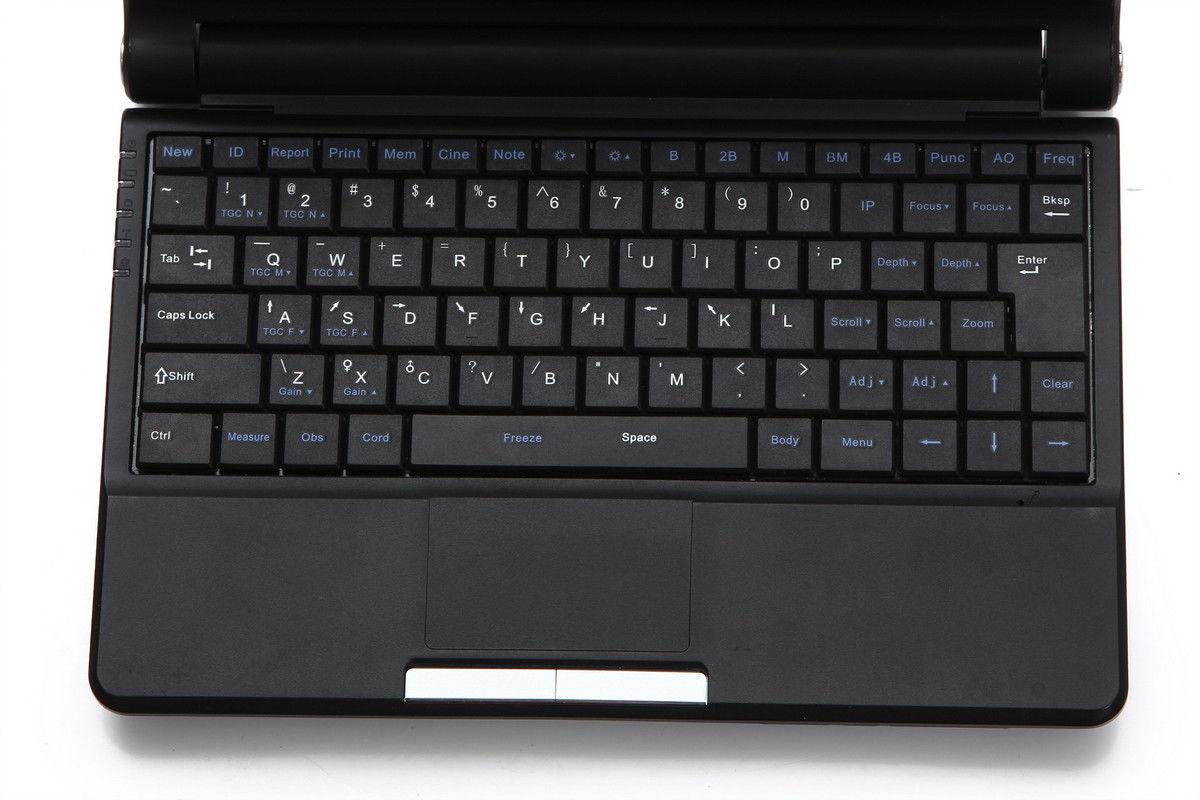

Portability and Ease of Use

This laptop ultrasound scanner is lightweight and compact, making it highly portable. Doctors can easily transport it between rooms or different facilities, ensuring they always have access to essential diagnostic tools. Furthermore, its user-friendly interface allows even those with limited ultrasound experience to operate it effectively. Therefore, healthcare professionals can quickly adapt and integrate it into their daily practices, maximizing efficiency.